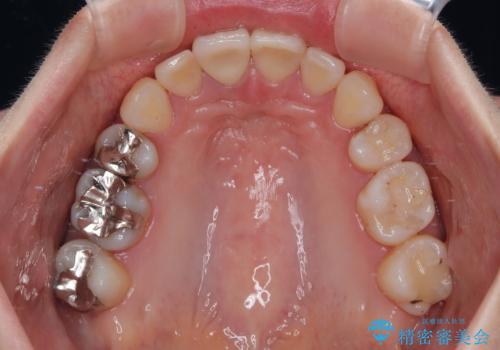

- 八重歯と上の前歯が出っ歯になっていることを気にして来院された患者様です。

横から見た際の口元の飛び出した印象も改善したいとのことで、上下左右の第一小臼歯4本を抜歯し、ワイヤー装置にて抜歯矯正を行うこととしました。

前歯の変色している歯は、神経組織が壊死していたため、矯正治療前に根管治療を実施し、矯正治療後にオールセラミッククラウンにて補綴治療を行うこととしました。